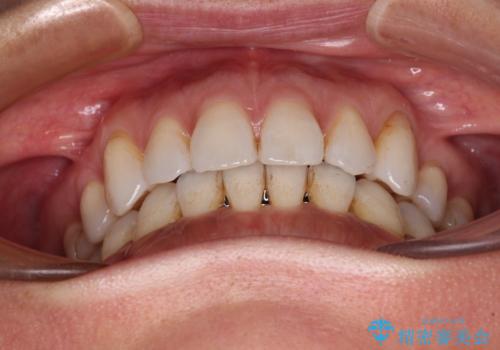

抜歯矯正の後戻りをインビザライン・ライトで解消

- 下顎前歯を中心に、以前行った矯正治療の後戻りが気になるとのことで来院された患者様です。

後戻りは軽度であったため、インビザライン・ライトにて治療を行うこととしました。

矯正治療後は、再度後戻りすることを極力回避するために、下顎前歯の舌側を細いワイヤーを用いて保定することとしました。